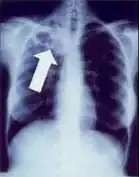

-

Chest X-ray of a person with advanced tuberculosis: Infection in both lungs is marked by white arrow-heads, and the formation of a cavity is marked by black arrows.